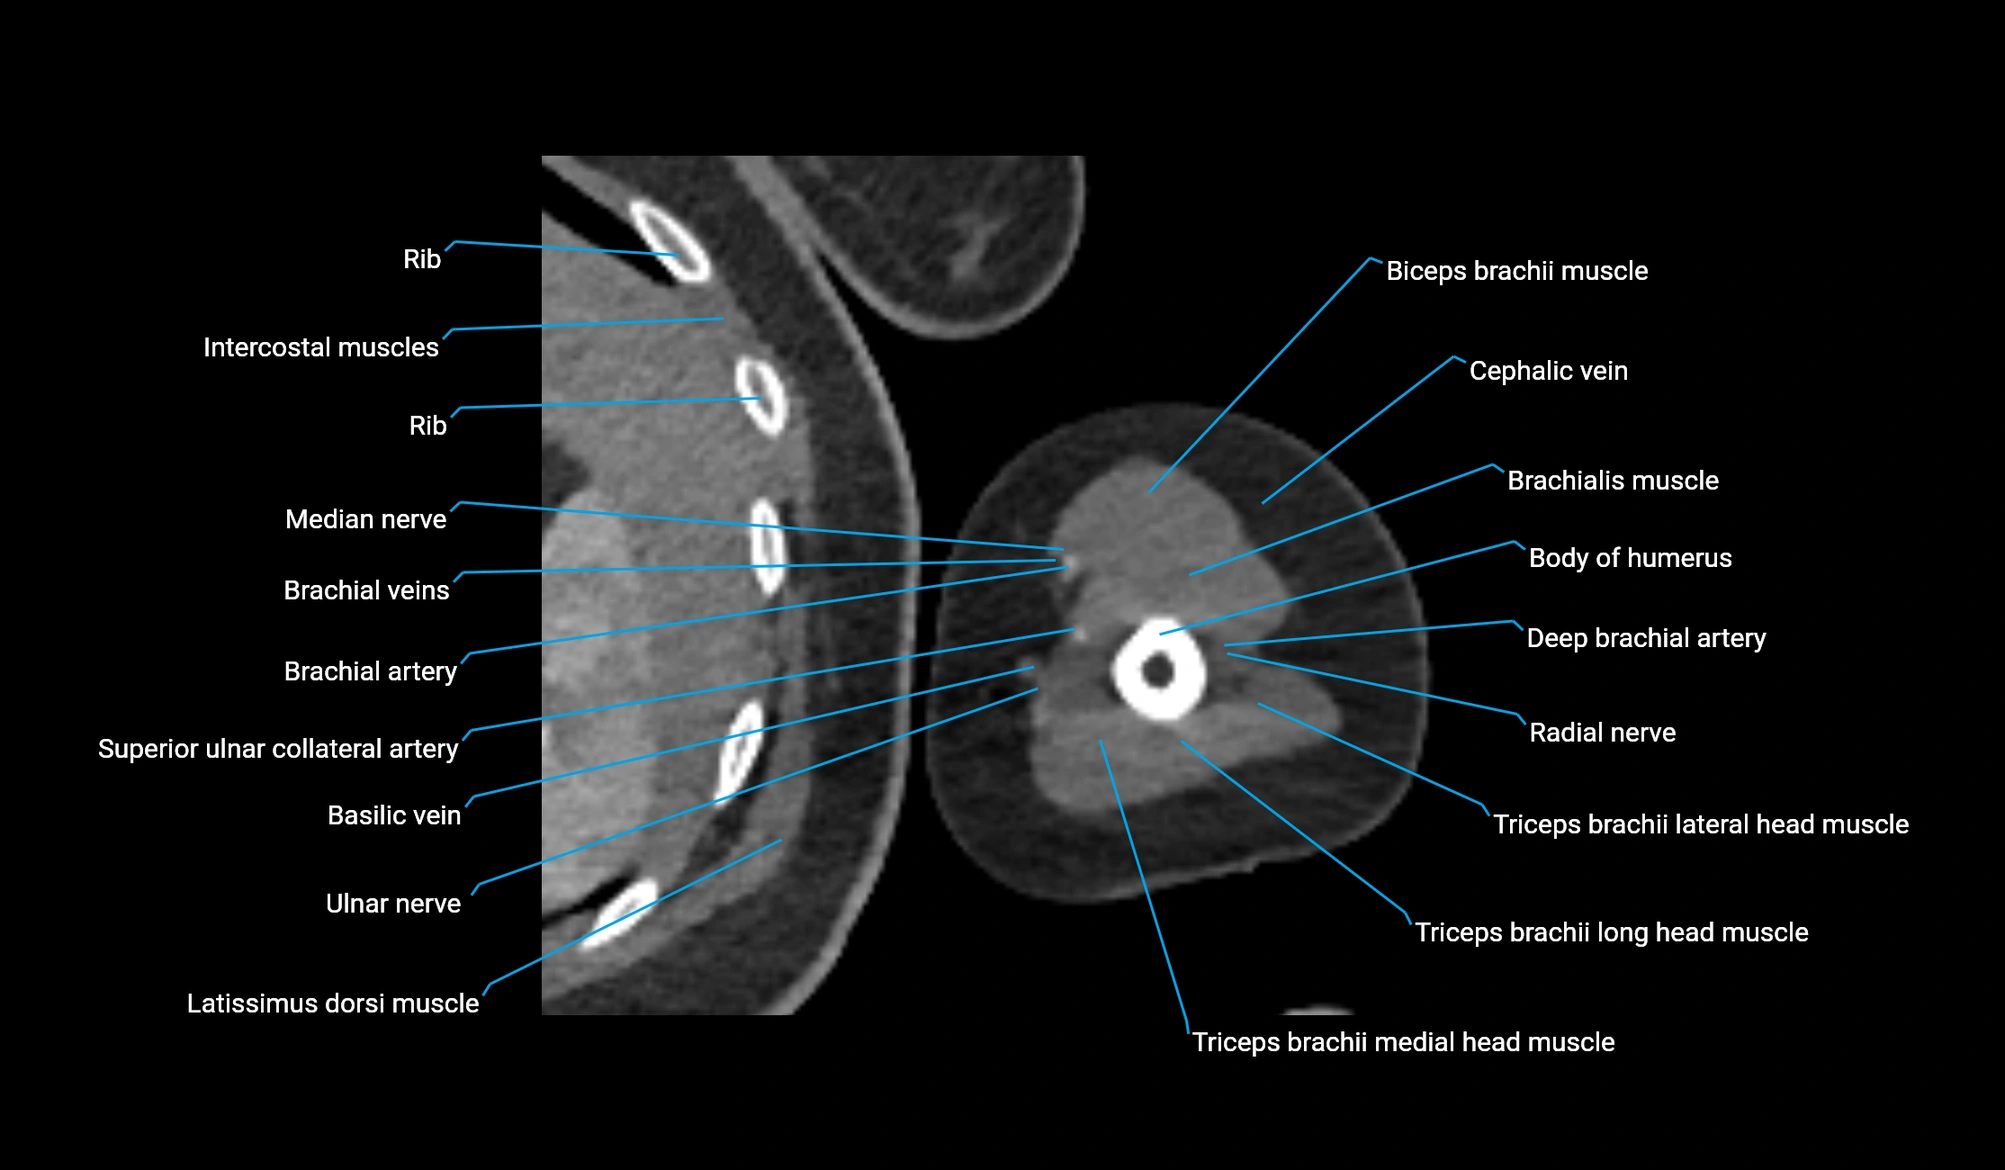

CT image